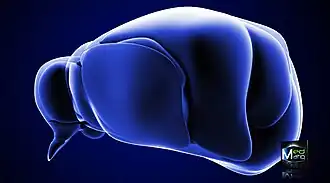

![]() Таламус человека на МРТ-снимке, отмечен стрелкой | |

![]() Таламус в передне-боковой проекции | |